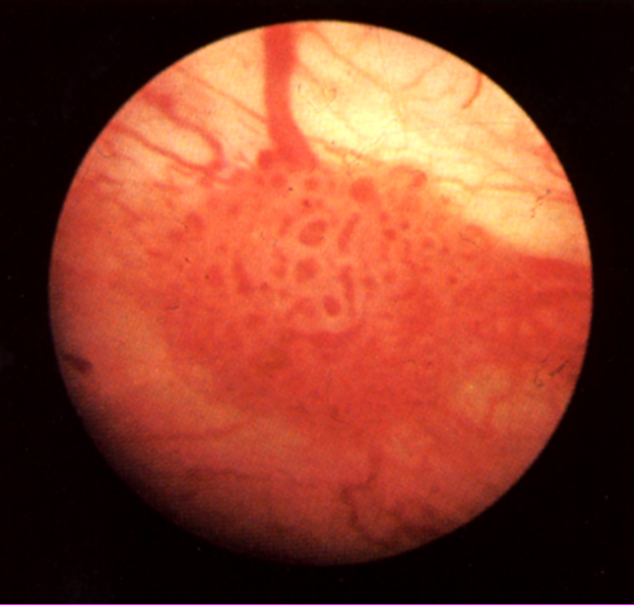

Investigatii endoscopice ale tumorilor vezicii

Investigatii endoscopice De la introducerea ei in practica si pana in prezent, cistoscopia a reprezentat si reprezinta examenul fundamental, obligatoriu si indispensabil pentru diagnosticul tumorilor vezicaCiteste tot ... 1016 cuvinte

Dimensiune mica

+ cu imagini |